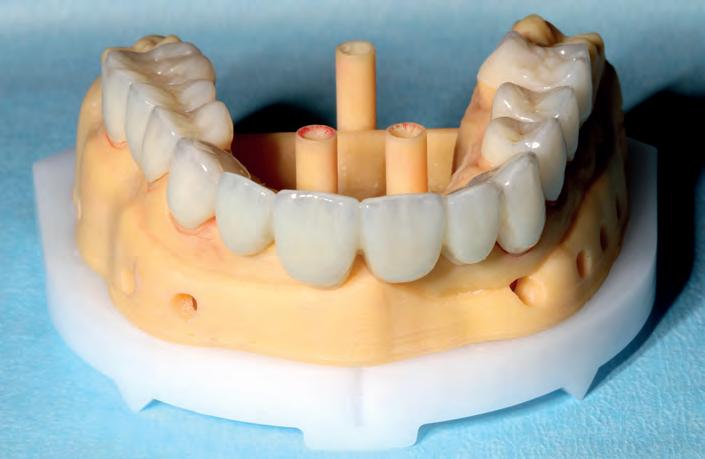

STEP 5 - CEMENTATION OF RESTORATIONS Due to the accuracy of intraoral scanning, the digital smile design and computer milled restorations, adjustments at this stage are now usually minor. I should point out that for single unit restorations, I work without printed models, unless in high aesthetics cases. However, for multiple units, I will choose to have printed models, so the technician and I can check all restorations at the same time. STEP 6 - FINAL REVIEW Giving the patient time to wear the new restorations, allows the patient to discover smaller details often missed when the he or she has been in the dental chair for a few hours and is still numb.

The restorations were milled on a Roland DWX52 DC from Aidite 3DPro u

SuperTranslucent Zirconia (Bleach shade), hand finished with tertiary anatomy, pre sinter stained with ZirconZahn Prettau effects, post sinter stained and glazed with MIYO. With the skill of the technicians, we could avoid the use of pink porcelain by shaping the bridge carefully, and because the patient did not have a high lip line.

The bridges and crowns were tried in with try-in paste (Vitique, water based) for final approval, and to check how all restorations fit individually and at the same time.

PICTURED RIGHT TOP: Restorations on model front below 2ND ROW LEFT: Restorations on model occlusal 2ND ROW RIGHT: Immediate post OP smile Immediate post OP face